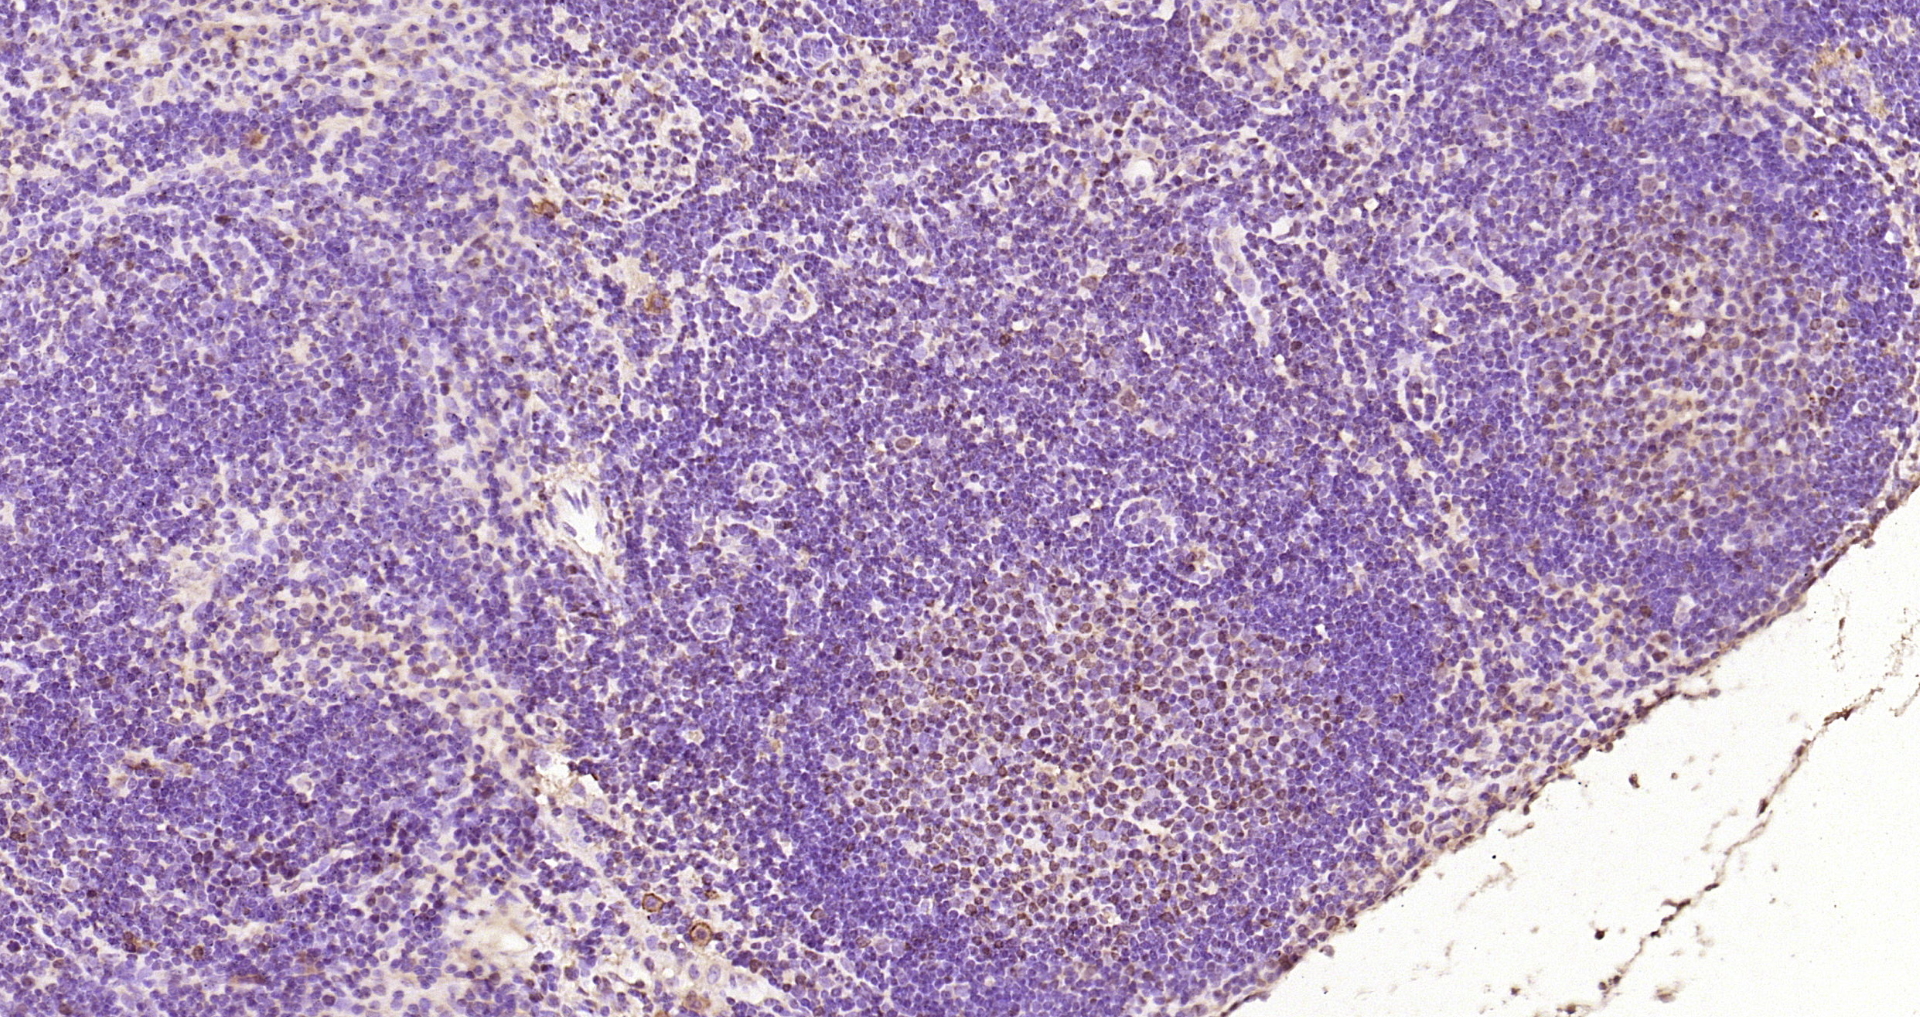

• IHC-P

IHC-P 1:200-400